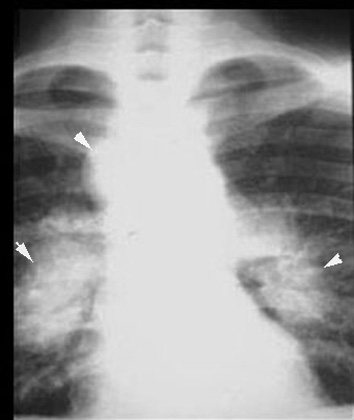

Sarcoidosis Type I

Type I: Adenopathy only